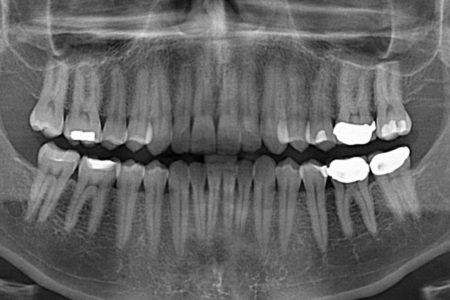

وی با انتقاد از بی‌توجهی به محافظت بیماران و همراه بیماران با وسایل پوششی مناسب برای سایر اعضای بدن که قرار نیست اشعه به آن تابیده شود، گفت: گاهی آنقدر به این موضوع بی‌توجهی  می‌شود که مردم نیز نسبت به آن آگاه نیستند. به عنوان مثال هنگامی که می‌خواهیم عکس رادیولوژی از دندان داشته باشیم باید غده تیروئید در گردن با پوشش مناسب سربی پوشیده شود تا جلوی تابش اشعه به آن گرفته شود که معمولا این اتفاق نمی‌افتد و مورد غفلت واقع می‌شود و این درحالی است که غده تیروئید غده مهم و حساسی در بدن انسان‌ها است. اهمیت این امر از نظر بهداشتی و حفاظتی تا حدی است که اگر دندانپزشکی این غفلت را انجام دهد جریمه این کار در حد تعطیلی مرکز است.

گورانی به منظور بیان این موضوع که در کشور ما استفاده بی‌رویه از پرتو در امور پزشکی زیاد است بیان کرد: مثلا در برخی از اورژانس‌های بیمارستان‌های عمومی از هر بیماری که وارد اوژانس می‌شود یک عکس رادیولوژی می‌گیرند آنهم در شرایطی که ممکن است اصلا لازم نبوده باشد و این هم در دسته پرتوگیری‌های غیرضروری قرار می‌گیرد. یا اینکه متاسفانه بعضی از بیمه‌ها برای پرداخت هزینه‌های دندانپزشکی فرد را مجبور می‌کنند حتما بعد از اتمام ترمیم دندان یک عکس رادیولوژی اضافی بگیرد که پیوست پرونده کنند. بدیهی است این اقدام غیر علمی با توجه به تعداد زیاد آسیب‌های دندان و نیاز گسترده به ترمیم دندان در کشور، سالیانه علاوه بر تحمل هزینه‌های گزاف به مردم، موجبات پرتوگیری قابل توجهی در افراد را فراهم می‌آورد.